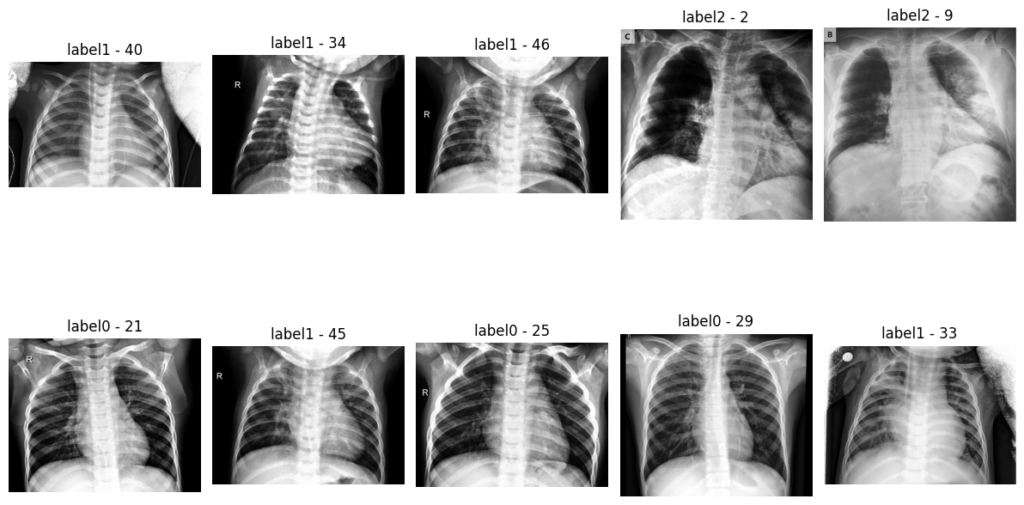

Dataset before transformation: